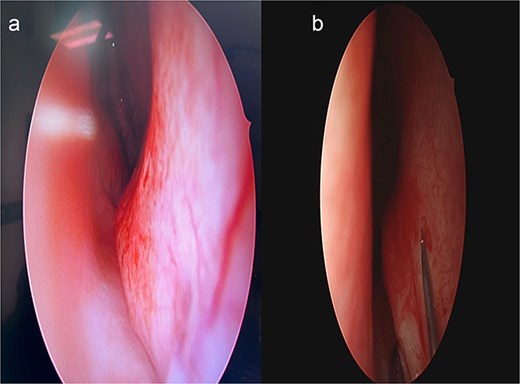

Post-operative care includes saline nasal sprays and head elevation. Patients are typically followed up at 1 week, 1 month, and 6 months postoperatively to assess healing and functional outcomes (Fig. 4).

Six-month postoperative follow-up endoscopic view demonstrating healed mucosa and patent nasal airway.